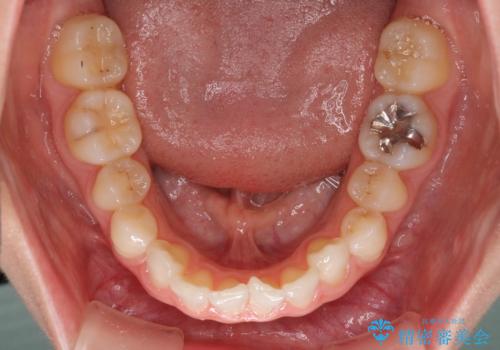

- 前歯のデコボコと左右の矮小歯を気にして来院された患者様です。

矮小歯の前後にスペースを作るようにインビザライン矯正治療を計画し、矯正治療後にオールセラミッククラウンによる補綴治療を行うこととしました。

アンカースクリューを用いて上顎歯列全体を後方移動させ、極力過蓋咬合も改善されるよう計画しました。